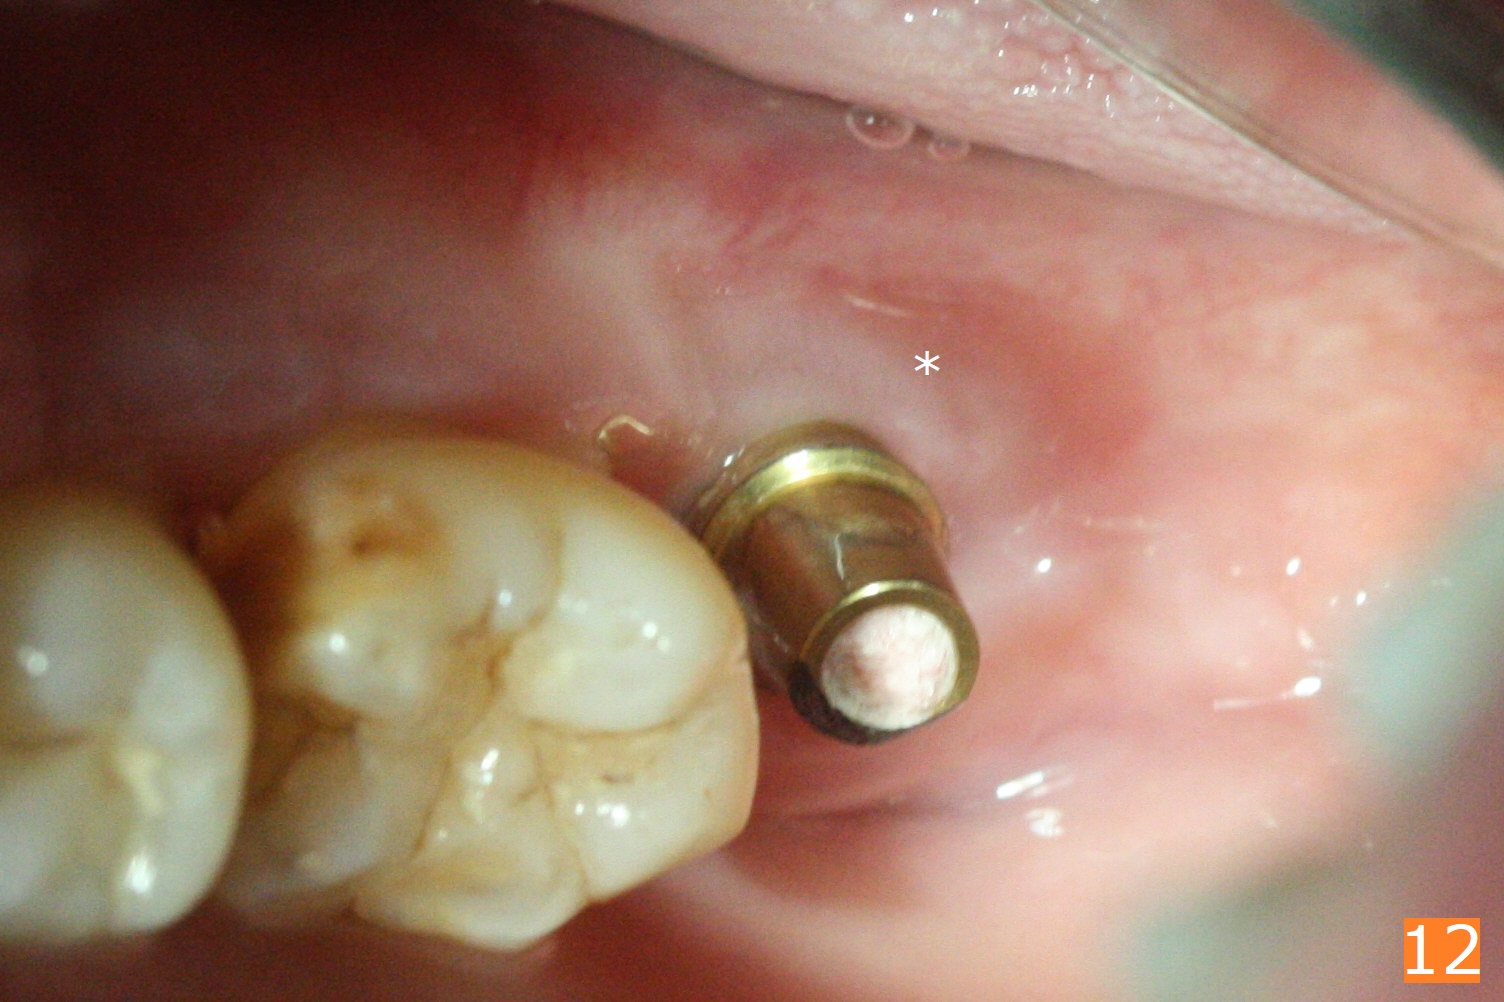

Socket shield (partial extraction therapies) is going to be conducted in this case to form a substitute buccal plate of the 2nd molar (Fig.1 *). The apex of the shield that contacts the 4.5x10 mm dummy implant cannot be removed because of poor access (Fig.2 * (12 mm offset)). Due to high bone density, a 4.5 mm drill has to be used in order to place a 5x7.3 mm definitive implant (Fig.3). In spite of the fact that the implant seems to be completely seated, the implant is ~ 1 mm supracrestal lingually. After implant removal, a 4.5x11.5 mm drill cannot reach the depth due to high bone density. 800 RPM instead of 50 RPM may help. When the implant is reseated, it appears to be .5 mm deeper than before clinically, although it looks incompletely seated in X-ray (Fig.4 <). The insertion torque is 60 Ncm. Allograft mixed with PRF is placed around the implant with cover screw, particularly mesiolinguodistal (Fig.4 *). The sockets of #17 and 18 are approximated with the help of 2 piece of PRF and collagen plug. The wound dehisces 9 days postop (Fig.5,6), although asymptomatic. Forced closure of the sockets with suture seems unnatural. An immediate provisional should have been fabricated. CT shows possible loss of part of bone graft (Fig.7). Regraft seems necessary in the appointment of uncover. Antibiotic is prescribed for another week. The gingiva seems healthy around the exposed healing screw 16 days postop (Fig.8). After debridement, the healing screw is then changed to a 4.5x5 mm healing abutment. The majority of the bone graft is lost without immediate provisional in 4 months (Fig.9 * (<: socket shield)). Then a 5.5x5 mm healing abutment is inserted for impression next appointment. A 5.2x4.5(4) mm cemented abutment is placed before impression (Fig.10). With socket shield (Fig.11 ^), the buccal gingiva looks more keratinized than the lingual one (Fig.12 *). Photos are taken immediately pre-cementation. Socket shield (*) covers the implant and abutment buccally (Fig.13 CT taken immediately pre-cementation).